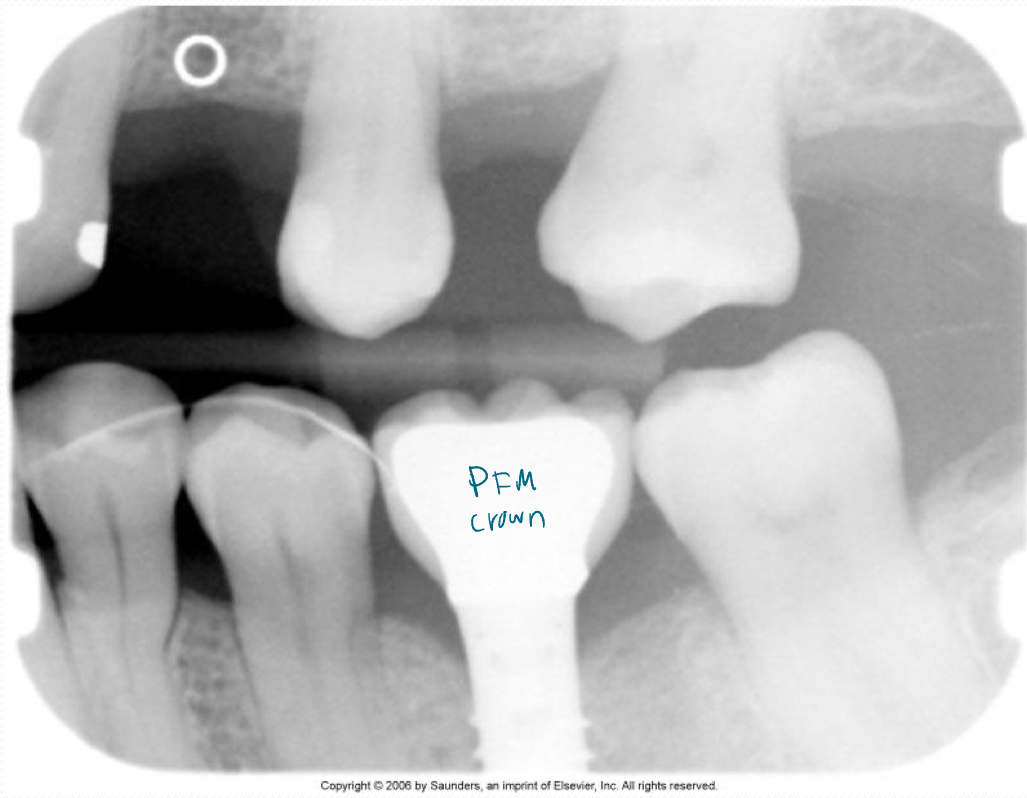

Porcelain-fused-to-metal crown (PFM)

PFM bridge